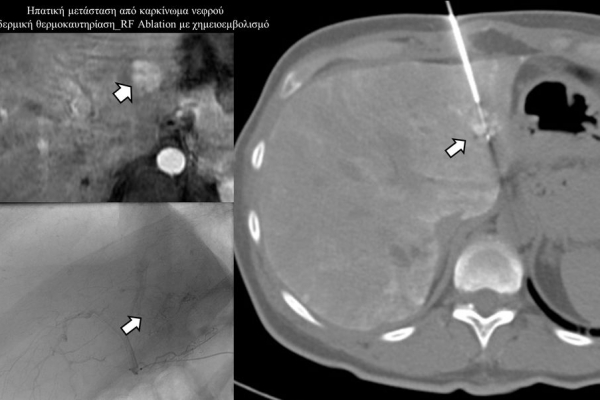

Πρόκειται για την πιο σύγχρονη τοπική θεραπεία όγκων του ήπατος, του νεφρού, του πνεύμονα, των οστών και των όγκων μαλακών μορίων. Παθοφυσιολογικά βασίζεται στην τοπική καταστροφή των καρκινικών κυττάρων με τη δημιουργία ιδιαίτερα υψηλών θερμοκρασιών εντός του όγκου. Αυτό επιτυγχάνεται με τοποθέτηση ειδικών ηλεκτροδίων εντός του όγκου υπό ακτινολογική καθοδήγηση (αξονικός τομογράφος ή υπέρηχος). Τα ηλεκτρόδια αυτά παράγουν υψηλή θερμοκρασία είτε με τη βοήθεια ραδιοσυχνοτήτων (RFablation), είτε με τη βοήθεια μικροκυμάτων (MWablation) και προκαλούν πηκτική νέκρωση των καρκινικών κυττάρων χωρίς να επηρεάζουν τα φυσιολογικά κύτταρα.Το αποτέλεσμα είναι μόνιμο.